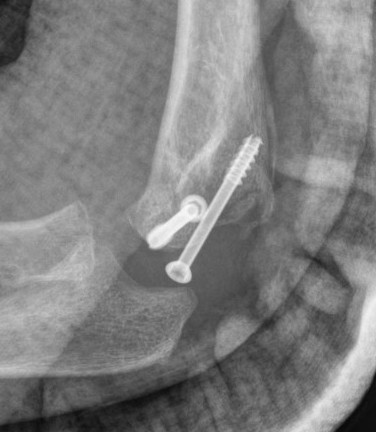

In situ screw fixation delayed nonunion

Results

Park et al J Paediatr Orthop 2015

- in situ fixation of 16 cases of nonunion with screw

- average 5 months post surgery with average 6 mm displacement

- all united

- 3/16 residual deformity